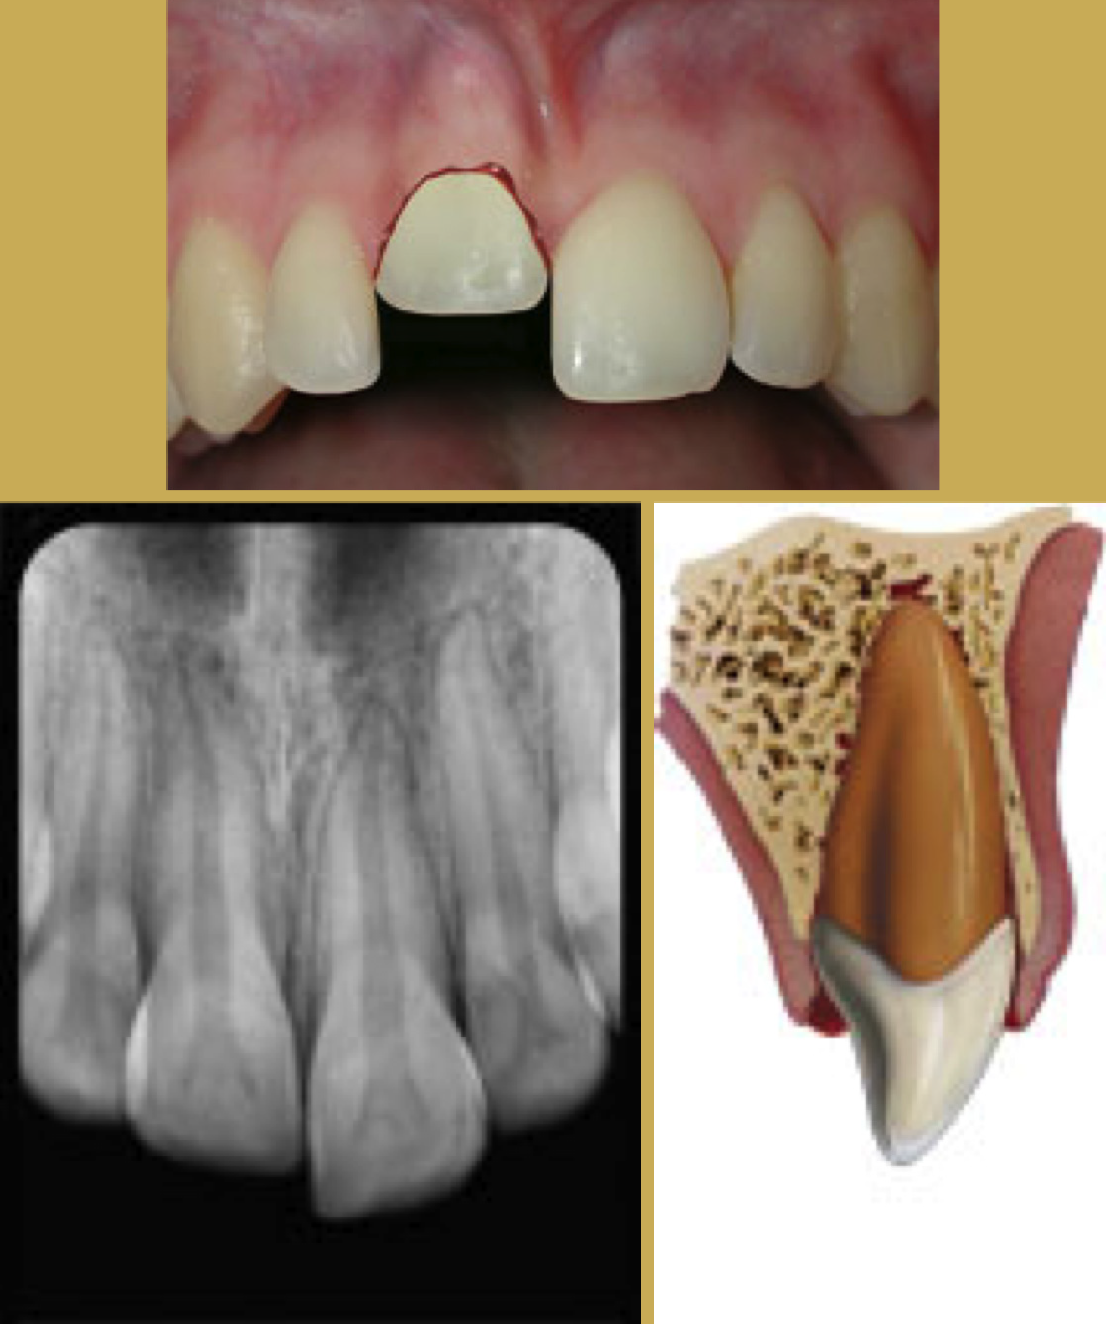

Fig 4. Images of Extrusion

Figure 4

Tooth Extrusion

The tooth is displaced partially out of the socket by the trauma (Figure 4). It is usually displaced palatally. The athlete should then be asked to bite down on a sterile gauze pad to temporarily splint the tooth in preparation for transport. Immediate removal from participation and referral to a trauma-ready dentist or emergency facility.44

Radiographically the tooth appears dislocated and empty at the end of the socket. Treatment is to try to reposition gently - local anesthetic is usually not needed. Check the occlusion to be sure there is no pressure on the tooth and use a non-rigid splint for two weeks. The dentist should periodically monitor the vitality of the pulp and perform root canal therapy if needed.